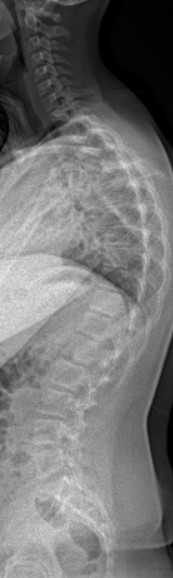

Birçok insan omurgada bir sorun olduğunda hemen skolyozdan şüphelenir, ancak her omurga problemi skolyoz değildir. Duruş bozuklukları ve skolyoz, sıkça karıştırılan ancak temelde farklı nedenlere dayanan iki ayrı durumdur. Bu blog yazısında, siz değerli okuyucalarımız için bu iki durumu daha iyi anlamalarını sağlamak ve hangi durumda profesyonel yardım almanız gerektiğini açıklayarak sizleri kliniğimize davet etmek istiyoruz.Duruş Bozukluğu Nedir?Duruş bozukluğu, omurganın doğal eğriliklerinin olması gerektiği şekilde hizalanmaması durumudur. Günümüz yaşam tarzı, özellikle uzun süreli masa başı çalışma, hareketsizlik, cep telefonu kullanımı gibi nedenlerle birçok kişide duruş bozukluğuna yol açabilir. Duruş bozukluğu genellikle:Omurgada kısmi veya geçici eğrilikler,Kas zayıflıkları veya dengesizlikleri,Hatalı oturma veya ayakta durma alışkanlıkları gibi sebeplerle ortaya çıkar.Duruş bozuklukları genellikle geri döndürülebilir ve erken aşamada tedavi edilirse kalıcı hasara yol açmaz. Kifoz (kamburluk) ya da lordoz (belin aşırı içe kıvrılması) gibi durumlar duruş bozukluğunun örnekleridir.Skolyoz Nedir?Skolyoz ise omurganın yanlara doğru anormal bir eğrilik geliştirdiği, genellikle kalıcı olan daha ciddi bir rahatsızlıktır. Bu eğrilik "S" veya "C" şeklinde olabilir ve omurga sağlığı açısından daha ciddi bir durum olarak kabul edilir. Skolyoz genellikle şu belirtilerle kendini gösterir:Omuz veya kalçada asimetri (bir tarafın diğerinden daha yüksek durması),Gövdenin bir tarafa kayması,Eğildiğinizde bel veya sırt bölgesinde bir çıkıntı.Skolyozun sebebi tam olarak bilinmemekle birlikte, genetik faktörlerin etkili olabileceği düşünülmektedir. Tedavi edilmezse ilerleyebilir ve ciddi sırt ağrılarına, solunum problemlerine ve hareket kısıtlılığına yol açabilir.Duruş Bozukluğu ve Skolyoz Arasındaki FarklarGeçicilik vs. Kalıcılık: Duruş bozuklukları genellikle kötü oturma ve duruş alışkanlıkları ile ortaya çıkar ve düzenli egzersiz ve postüral farkındalık ile düzeltilebilir. Skolyoz ise kalıcı bir omurga eğriliğidir ve kendiliğinden düzelmez, profesyonel tedavi gerektirir.Hafif vs. Ciddi Eğrilikler: Duruş bozuklukları omurganın doğal eğriliğinin bozulması ile karakterize olurken, skolyozda omurga anormal bir şekilde yana doğru eğrilir.Tedavi Yöntemleri: Duruş bozukluğu genellikle egzersiz, klinik pilates, postür düzeltici cihazlar veya kayropraktik tedavi ile düzeltilebilir. Skolyozda ise fizyoterapi, Schroth terapisi gibi spesifik egzersiz programları veya ciddi vakalarda cerrahi müdahale gerekebilir.Hangi Durumda Yardım Almalısınız?Eğer postürünüzde hafif bir bozukluk hissediyorsanız ve sırt ağrıları yaşamaya başladıysanız, bu durumu düzeltmek için vakit kaybetmeden bir uzmana başvurmak önemlidir. Duruş bozukluğu zamanında müdahale edilirse skolyoza dönüşmeden düzeltilebilir. Skolyozdan şüpheleniyorsanız, omurga eğriliğinizin ilerlemesini durdurmak için bir uzmandan profesyonel destek almanız gerekebilir.Kliniğimizde Sunduğumuz HizmetlerBizimle birlikte, omurga sağlığınızı korumak ve hem duruş bozukluklarını hem de skolyoz gibi daha ciddi durumları yönetmek için profesyonel bir destek alabilirsiniz. Kliniğimizde uzman kadromuzla, duruş analizi, kayropraktik tedavi , kişiye özel egzersiz programları , Klinik Pilates , Fizyoterapi Ve Rehabilitasyon, Schroth Tedavis ile omurganızı güçlendirmek ve ağrısız bir yaşam sürmenize yardımcı oluyoruz.Sonuç OlarakDuruş bozuklukları ve skolyoz arasındaki farkları anlamak, omurga sağlığınız için doğru adımları atmanızı sağlar. Eğer bu iki durumdan herhangi birinden şüpheleniyorsanız, daha fazla bilgi almak ve değerlendirme yaptırmak için kliniğimize başvurabilirsiniz. Sağlıklı bir omurga için doğru teşhis ve tedaviye zamanında başlamak büyük önem taşır.Unutmayın, omurga sağlığınız genel sağlığınızın temelidir. Erken müdahale ile duruş bozukluklarını veya skolyozun ilerlemesini durdurabilir, yaşam kalitenizi artırabilirsiniz.Kliniğimizle iletişime geçmek ve ücretsiz duruş analizi için randevu almak için hemen bize ulaşın!